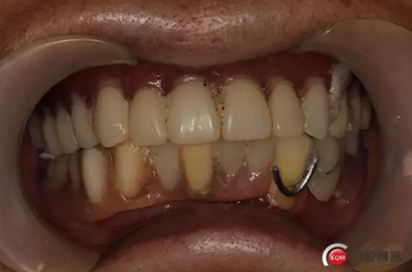

戴牙:試戴,拍片確定邊緣密合后調(diào)整咬合,試戴一周后患者適應(yīng),咬合良好,基臺(tái)加力30N.CM,粘接劑粘固,去除多余粘結(jié)劑,拍片確定有無(wú)粘接劑殘留,并進(jìn)一步微調(diào)咬合

6)6個(gè)月后復(fù)查,修復(fù)體密合性均良好,修復(fù)效果符合預(yù)期,醫(yī)囑患者做好口腔衛(wèi)生預(yù)防種植體周?chē)?/p>